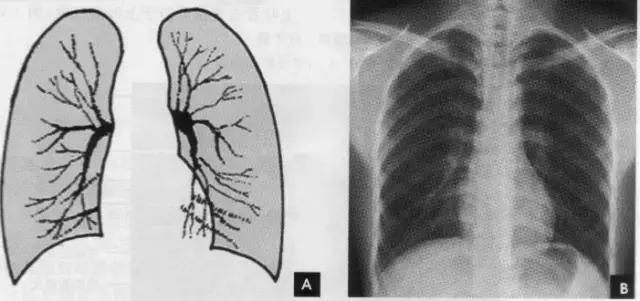

(一)肺野

纵隔两旁含气的肺在胸片上所显示的透明区域称肺野,其透明度随呼吸而改变,深吸气时肺内含气量增多,透明度增高,呼气时则相反。

为便于指明病变的部位,通常人为地将一侧肺野纵向分为三等分,即内、中、外带。又分别在两侧第2、4肋骨前端下缘划一水平线,将肺野横向分为上、中、下三个肺野。一般将第1肋圈外缘以内部分称为肺尖区,将锁骨以下至第2肋圈外缘以内部分称为锁骨下区,将最下肺靠近膈面的部分称为肺基底部(如上图)。

(二)肺叶

在胸片上不能显示各肺叶的界限,但可通过正侧位胸片上显影的叶间胸膜推断肺叶的解剖范围。右肺分为上、中、下三叶;左肺分为上、下二叶(如上图)。